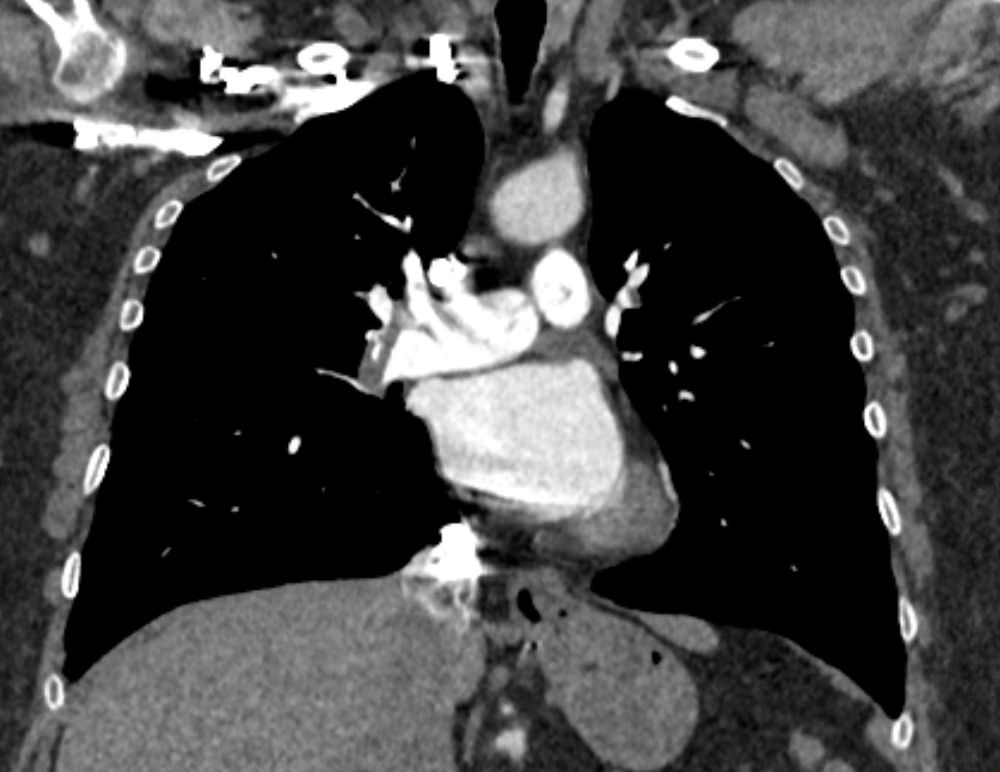

Наиболее информативным, при этом быстрым и неинвазивным (то есть без вмешательства в организм пациента), методом диагностики патологии легочной артерии является мультиспиральная компьютерная томография (КТ-ангиография). Методика основана на использовании рентгеновского излучения в сочетании с цифровой обработкой данных для получения трехмерных изображений сосудистой системы.

Для визуализации кровеносных сосудов в обязательном порядке применяется контрастное усиление. Для этого в вену пациента вводится йодсодержащий контрастный препарат, который попадая в кровоток активно поглощает рентгеновские лучи и ярко контрастирует сосудистую систему, в том числе легочной артерии, на фоне окружающих тканей. Использование контраста дает возможность визуализировать даже мелкие артерии и выявить патологию.

В наших диагностических центрах КТ-ангиография легочной артерии проводится на современных мультиспиральных компьютерных томографах экспертного уровня TOSHIBA AQUILION. Оснащение аппаратов позволяет получать детальные снимки и трехмерные изображения сосудистой системы легочной артерии, при этом применение скоростной мультисрезовой методики сканирования значительно снижает уровень лучевой нагрузки на пациента.